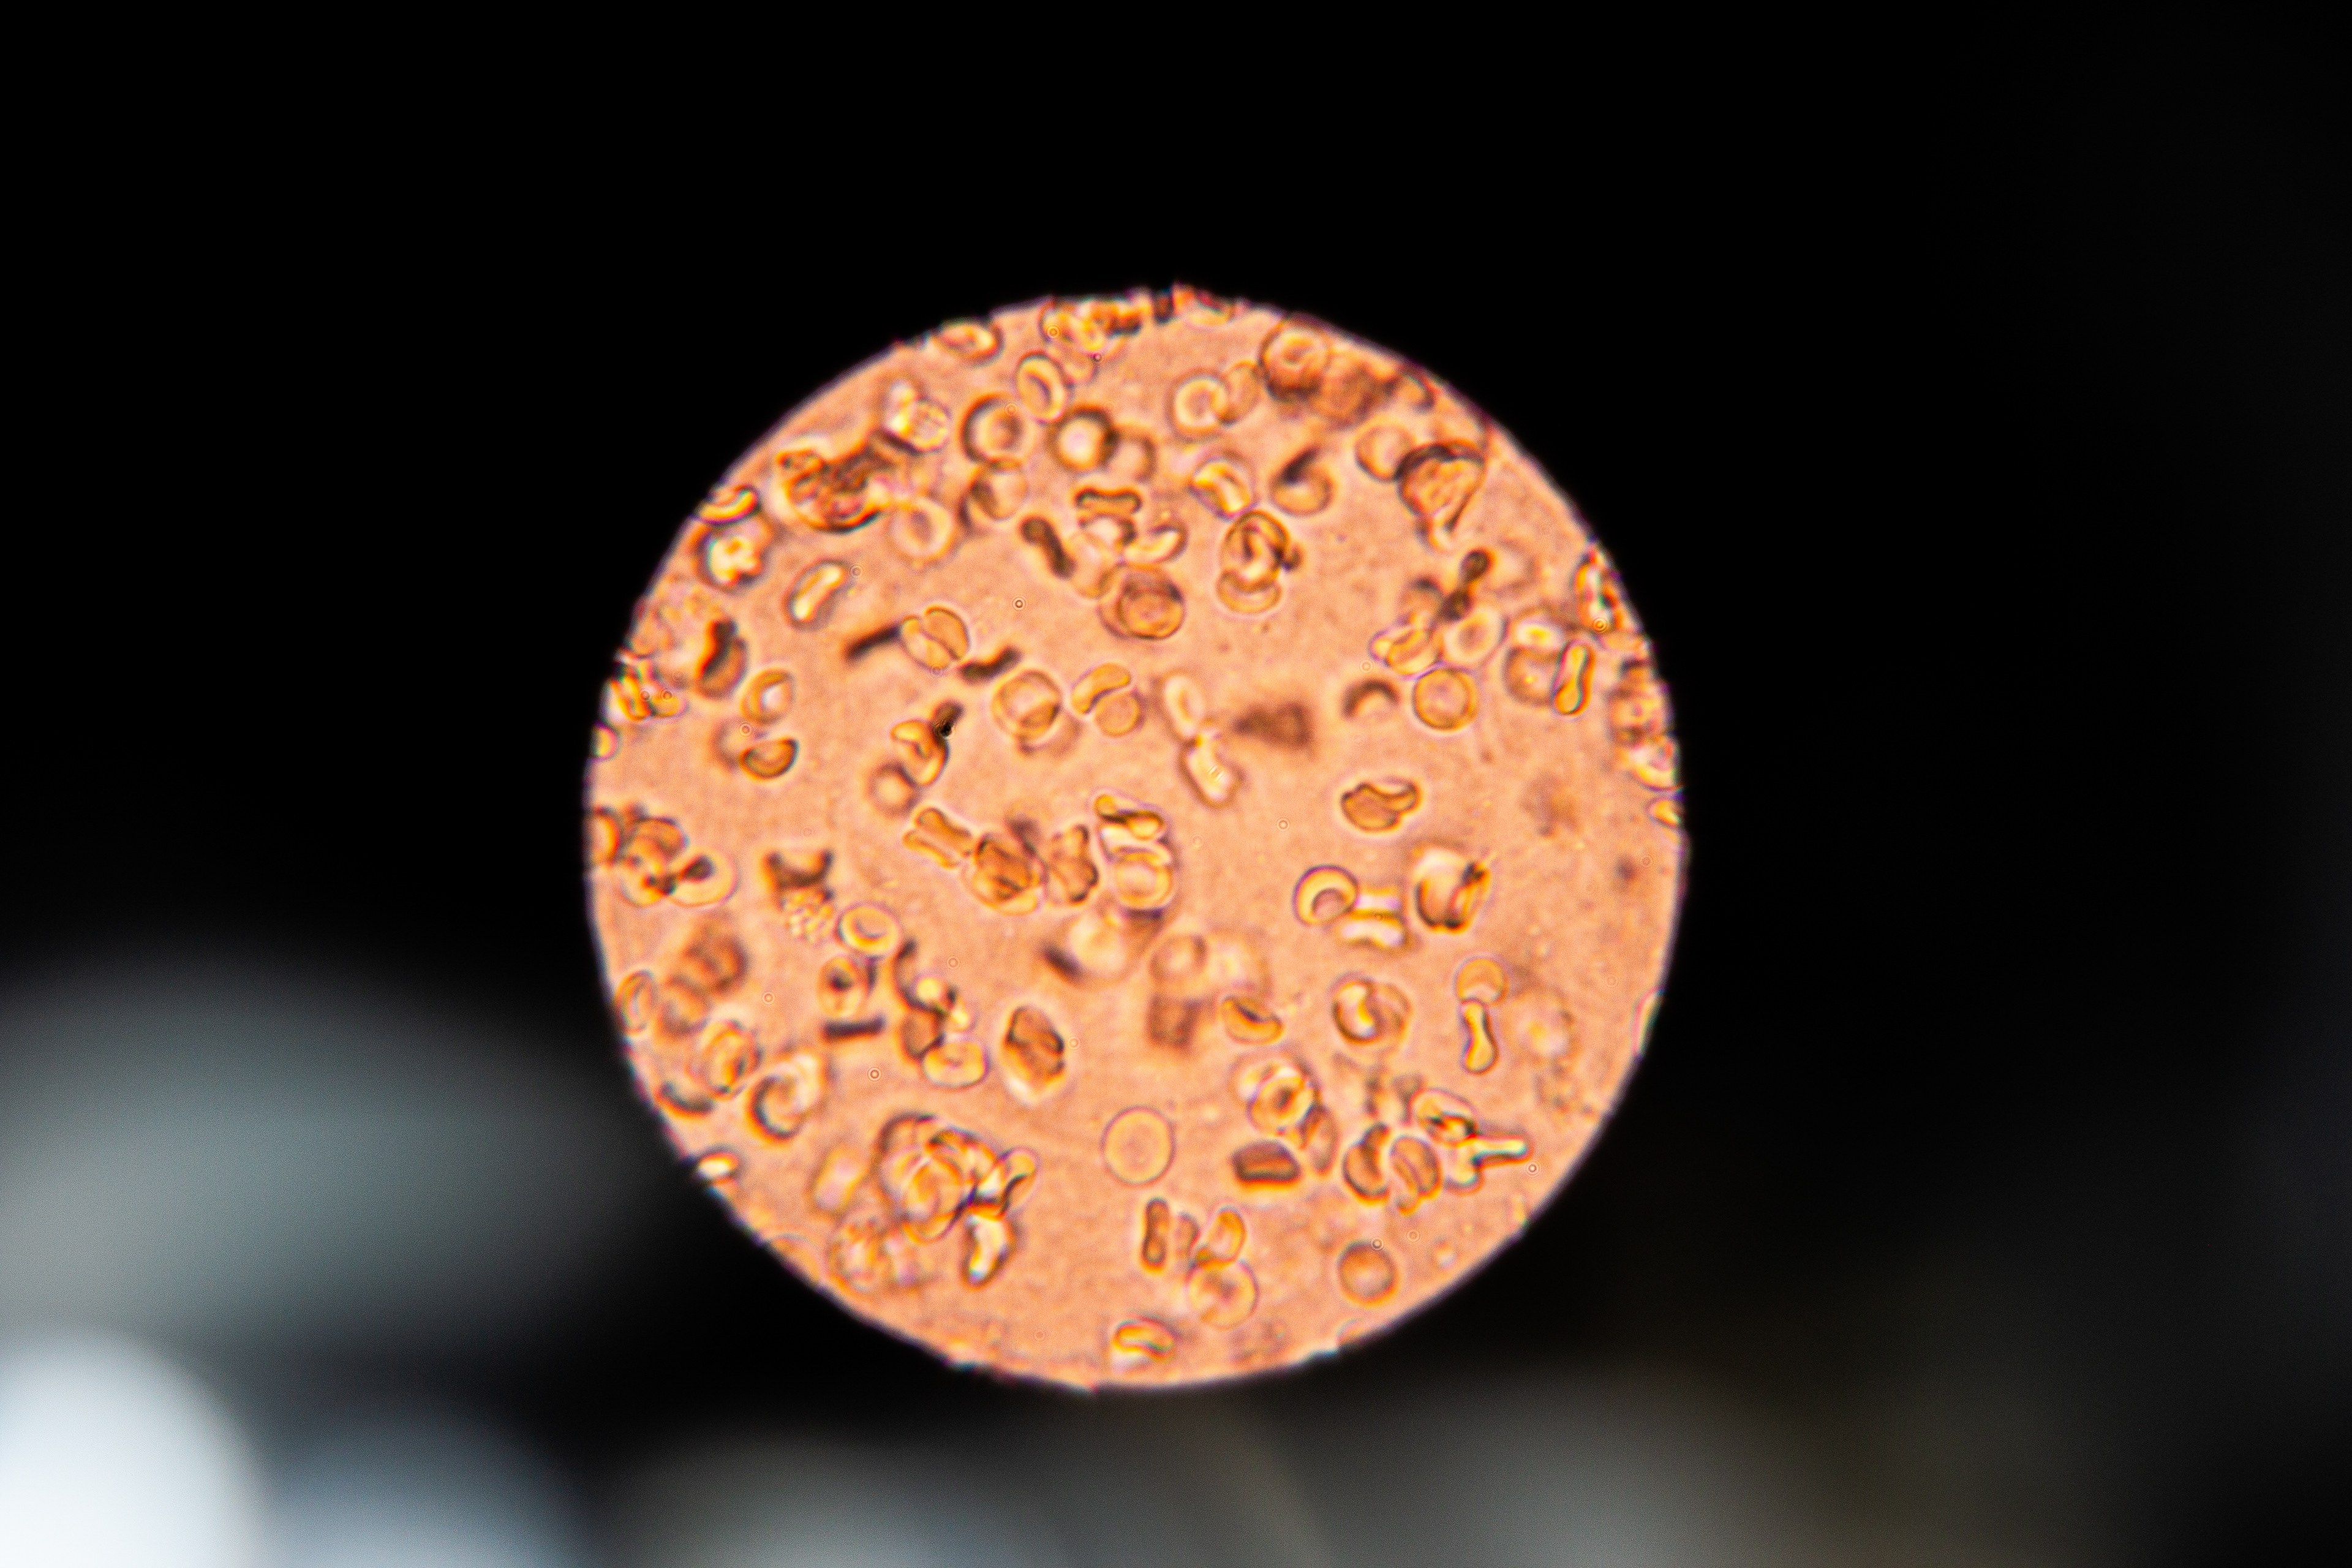

This got me curious. So, I collected and analyzed my own menstrual blood. First I took a look at my venous blood from my small finger and then compared it to my menstrual blood. The following pictures show my menstrual blood at different magnifications:

Menstrual Blood 400x